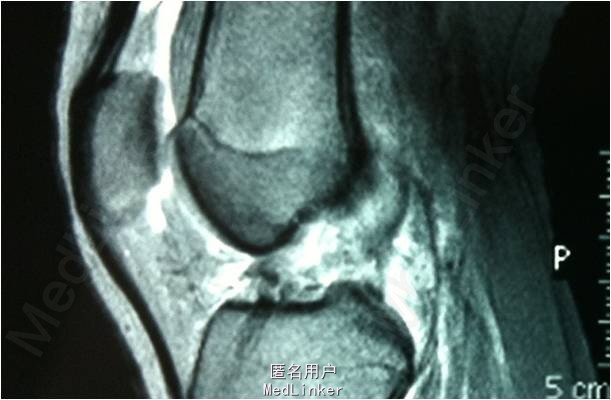

查体:双下肢无畸形,左膝关节稍肿胀,皮温正常,关节间隙压痛,麦氏征(+),蹲走试验(-),过伸试验(-),过屈试验(+),浮髌征(±),髌骨加压研磨试验(-),前抽屉试验(+),后抽屉试验(-),侧方应力试验(-),lachman征(+),关节活动度10-120度,股四头肌无明显萎缩,肌力正常;肢端血运、感觉、活动正常。右下肢及双上肢其余关节未见明显异常。MR提示:左膝关节前交叉韧带损伤

诊断:左膝前交叉韧带损伤。行左膝关节镜检及前交叉韧带重建术